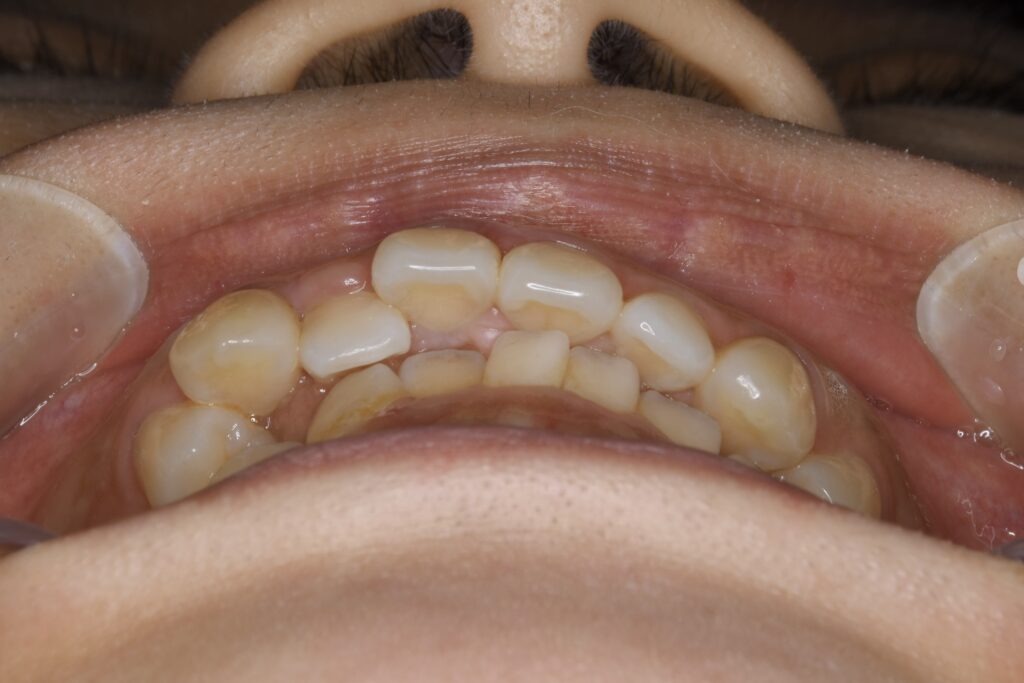

AFTER

治療内容 上下とも歯を2本抜いて、上の前歯を後方に引きながら、でこぼこを治しました。

使用装置 マウスピース矯正装置(インビザライン)

治療期間 1年7ヶ月

通院回数 13回

費用 91万円程度(税別)   270